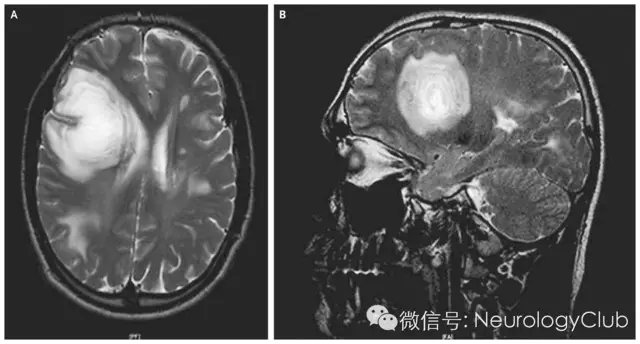

头颅MRI是诊断BCS的重要手段。在各种扫描序列上均可见典型的圆或类圆形影像(“煎鸡蛋”样 fried egg-like)。在T1WI、T2WI可见年轮样同心圆带;FLAIR像更清楚反映出所有病灶的大小及同心圆带。并不是所有BCS都可见典型同心圆带,同心圆带具有象限性,即并不是完整的圆形,可表现为部分象限,呈扇形样的跑道。DWI信号逐渐减弱,甚至部分呈低密度,而颅内肿瘤DWI信号常常逐渐增强。MRI增强扫描后,典型者亦可呈同心层强化,主要表现为T1WI或TWI等密度处的强化。T1WI低密度(或T2wI高密度)信号代表脱髓鞘区域,T1Wl或T2WI等密度处代表髓鞘脱失极轻。